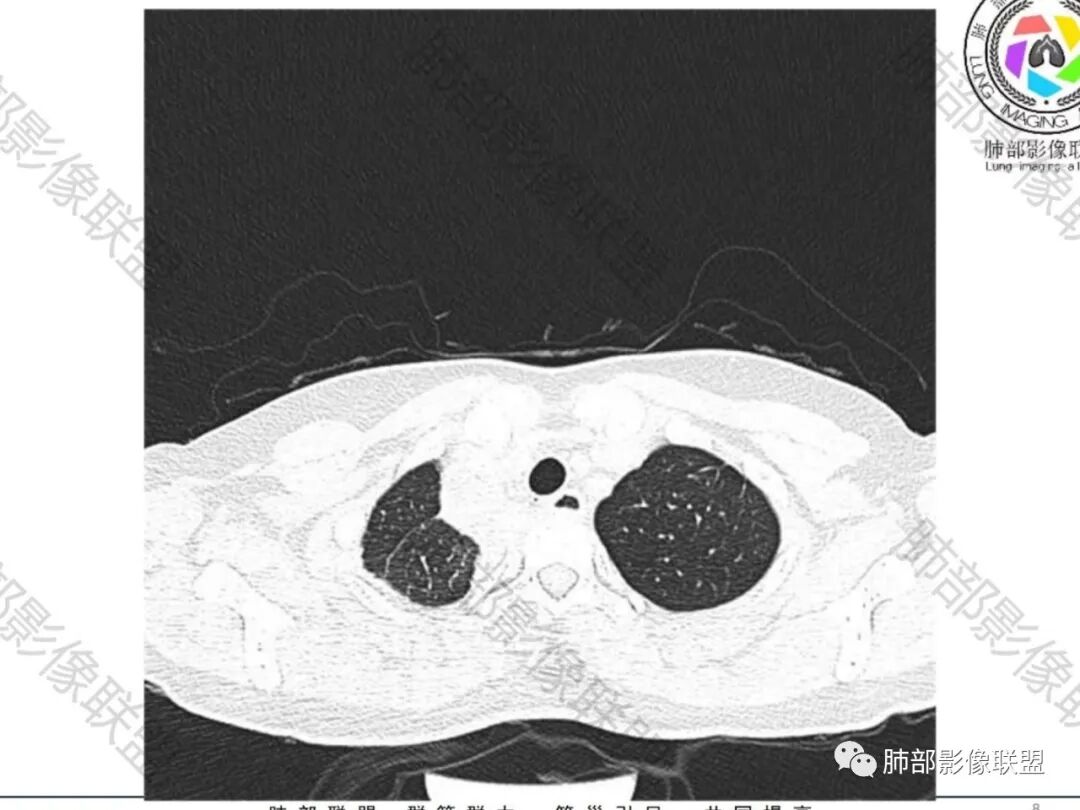

一切∮随缘:双侧胸廓塌陷,以右侧为主,右侧肋间隙狭窄,双肺上叶及右肺下叶胸膜下多发不规则肿块,密度不均匀,内部可见条片状,不规则钙化影,部分钙化不密实,双肺多发纤维索条影,似陈旧性病灶,双侧胸水,临床年轻女性,无感染症状,考虑考虑结核淀粉样变,转移性钙化,弥漫性肺骨化病。

丽:双肺散在索条及条片状高密度影,边界清晰,部分实变内可见钙化,支气管管壁增厚,双肺胸膜局限性增厚伴钙化,部分肋骨密度增高,首先考虑结核并淀粉样变性,鉴别转移性钙化,肿瘤样钙质沉着症,胸膜间皮瘤。

尘缘:青年女性,痰中带血,胸痛2月,无发热盗汗,实验室检查,有贫血,总蛋白降低,血沉情况未知,肿标基本正常。影像表现:双上肺小叶间隔增厚,双侧胸膜广泛不规则增厚,胸膜下多发肿块伴不规则钙化,右侧肋骨破坏。纵隔淋巴结肿大不明显,双肺门淋巴结肿大,部分融合,分析思路:一、感染性病变,1、结核,青年女性,胸膜增厚,多发肿块伴钙化,有咳嗽胸痛,痰中带血,要考虑,但无结核中毒症状,病史仅两月却钙化太明显,肺内没有明显树芽征,存疑,2、其他感染,无炎性指标支持,白细胞不高,可能性小。二、非感染性病变,1、尘肺,胸膜增厚,钙化,胸膜下钙化性肿块,要考虑,但肺内无粉尘结节,无职业史,可能小。2、转移性钙化,无肾脏病史,无血清钙磷代谢异常指标支持,肺内间质无钙沉积改变,基本排除。三、肿瘤性病变,1、肺癌伴转移,双上肺有小叶间隔增厚,双肺门有淋巴结肿大,要考虑,但青年女性,病史两月,钙化太多太广泛,肿标基本正常,可能性小。2、骨肉瘤转移。15-30岁青年人,是骨肉瘤高发年龄,肺内多发成骨样钙化转移灶,双上肺小叶间隔增厚符合癌淋样表现,右侧肋骨破坏,要高度怀疑,需要详细询问病史及手术史。3、软骨来源肿瘤伴肺内转移,右侧肋骨虽有破坏,但无明显软骨样破坏及钙化。可能小。4、其他肿瘤伴转移,青年女性,其他恶性肿瘤能广泛发生钙化性转移的可能性小。综上所述:骨肉瘤伴右侧肋骨及胸膜转移,胸膜下转移,肺内癌淋可能最大,结核不完全除外,下一步需要,仔细询问病史,如果有骨肉瘤史,则基本确诊,如果没有,需要进一步问询呼吸系统症状,病程,以前的影像对照,了解肾脏情况,查血清钙磷指标。

空洞形成,一般伴随的很多都是气道的播散,树芽征

这个病例没有